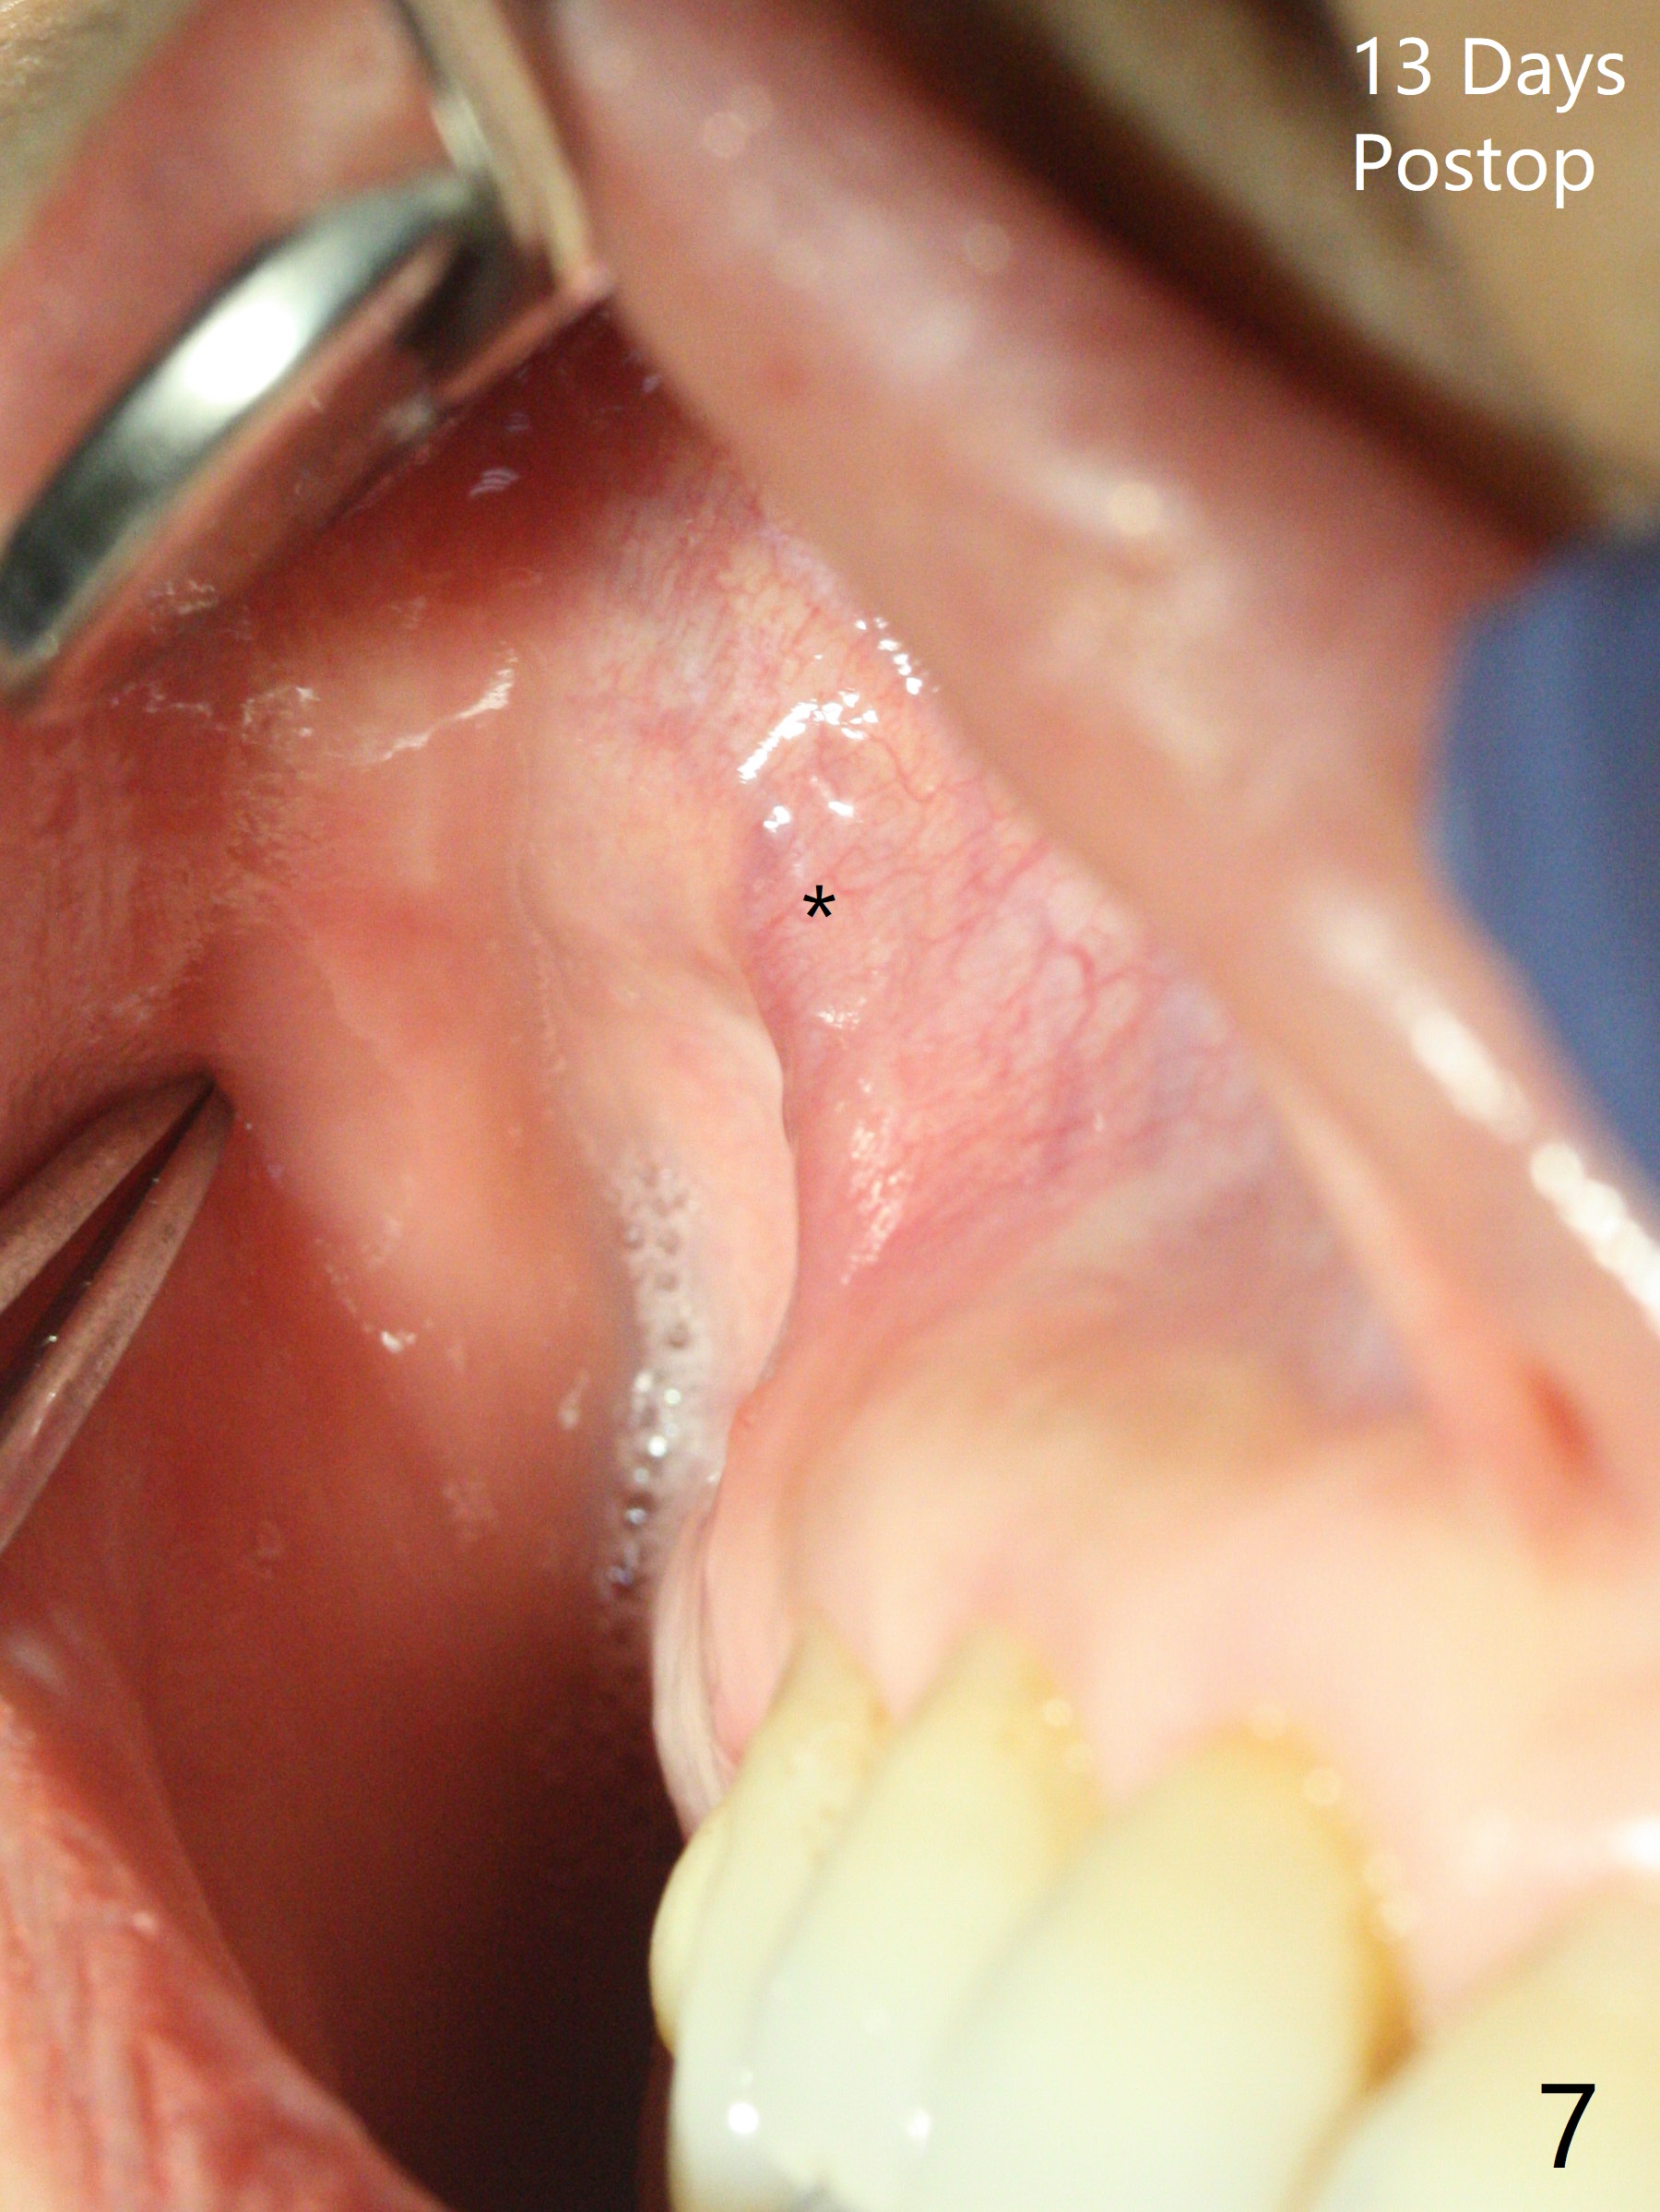

After extraction of the tooth #4 with fistula (Fig.1), the buccal bony defect is superior to the fistula. Before placement of a 4.5x17 mm tissue-level implant (Fig.2) and after osteotomy for bone-level one, PRF and mixture of autogenous bone and allograft are pushed from the socket through the buccal defect for repair (Fig.3 arrowheads). The trajectory of the implant (Fig.4) is consistent with design (Fig.5). The fistula reduces in size and in redness, while the apical elevation (as related to the underlying bone graft) remains prominent 13 days postop (Fig.6,7 *). The distal defect has been apparently repaired 9 months postop (Fig.8 *, as compared to immediately post bone graft in Fig.2). The distal defect has been apparently repaired 9 months postop (Fig.8 *, as compared to immediately post bone graft in Fig.2). The fistula disappears (Fig.9).